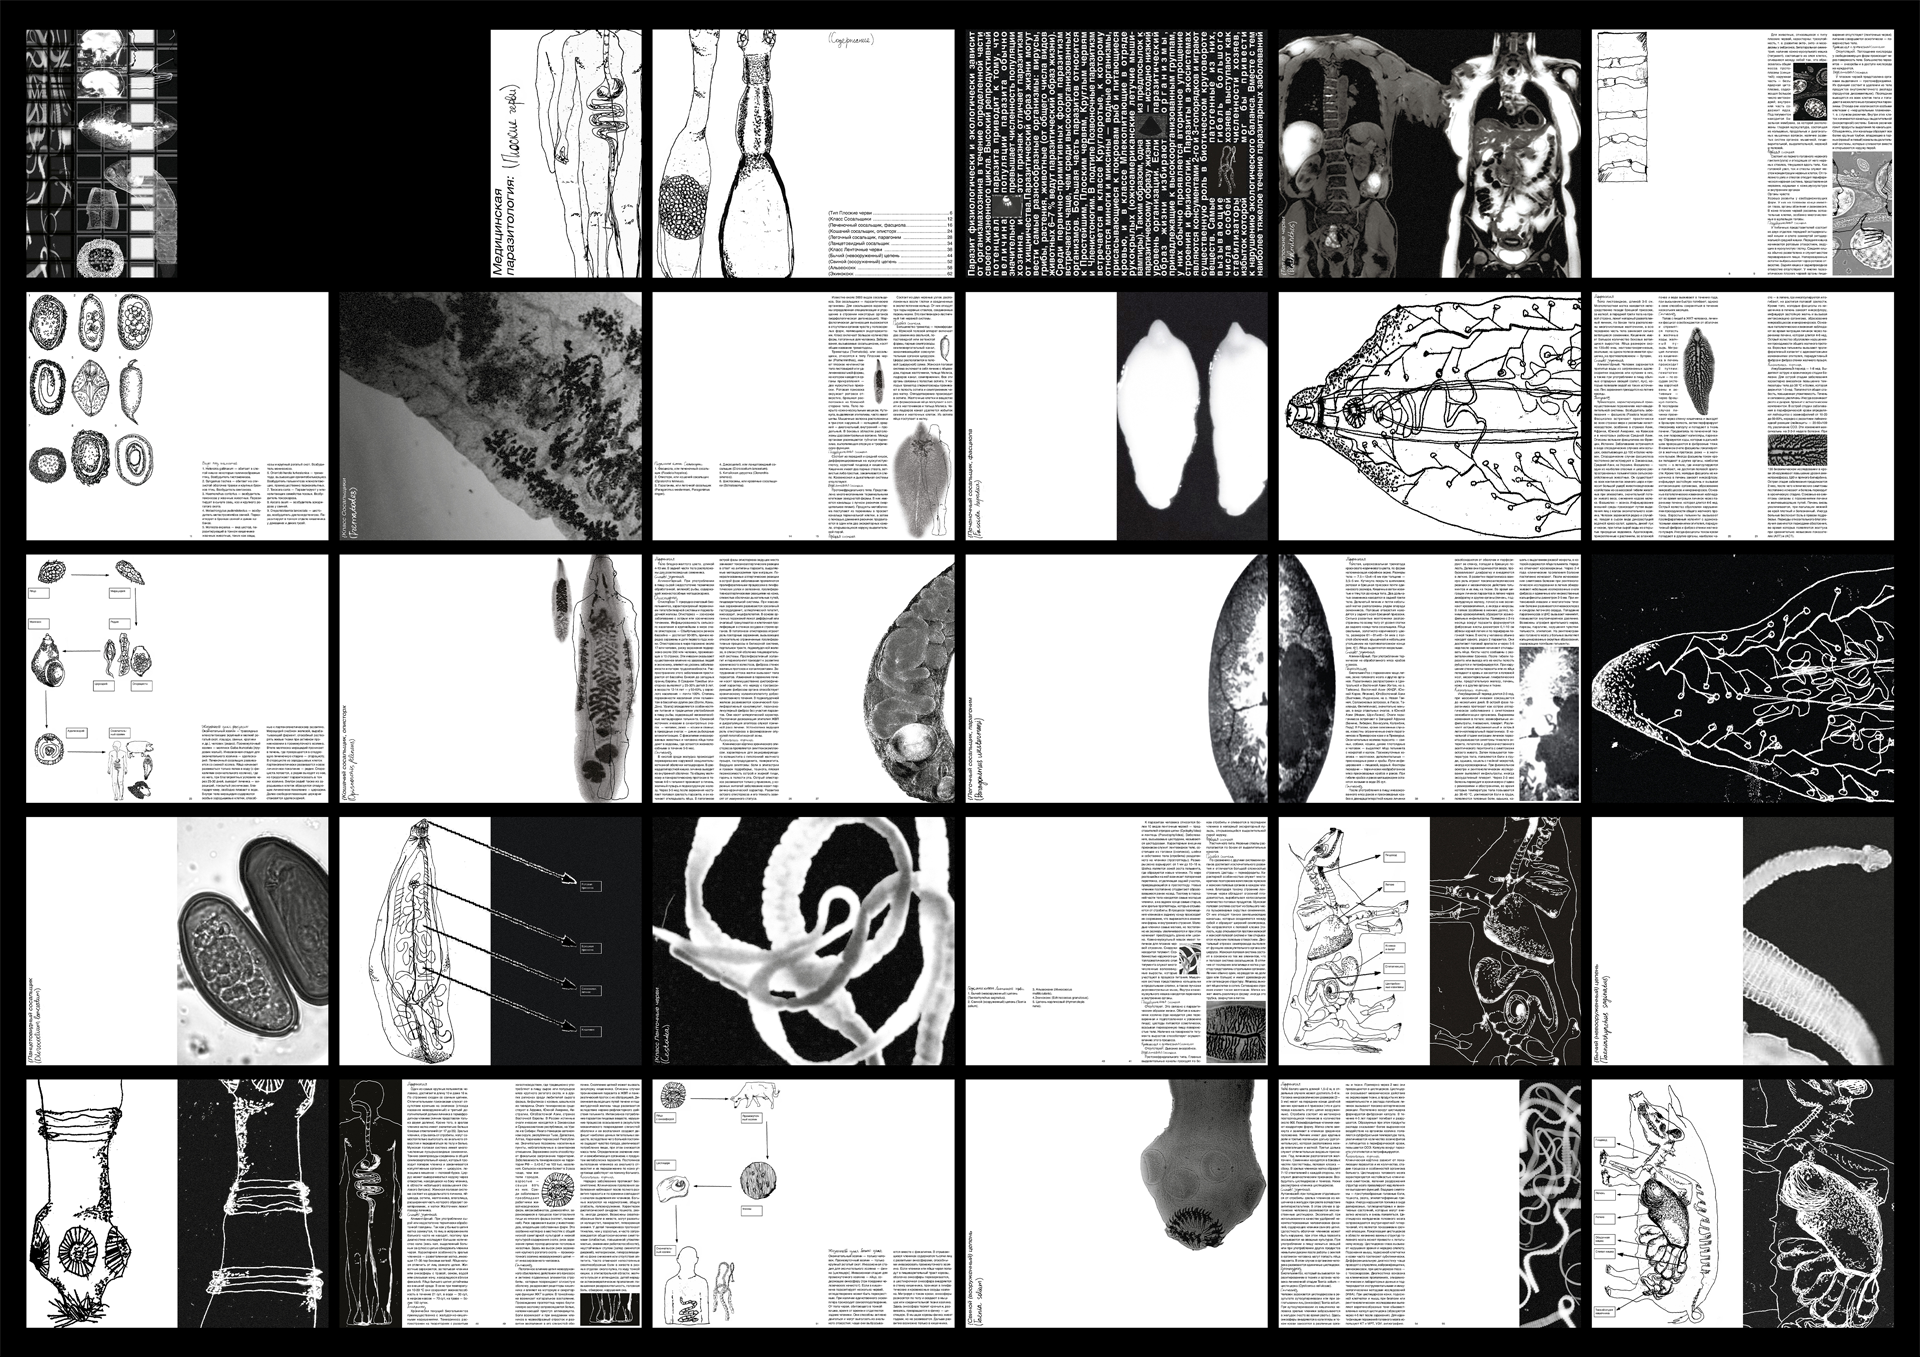

«Медицинская паразитология: Плоские черви» — компактный справочник, посвящённый паразитическим плоским червям, созданный под вдохновением от старых медицинских и биологических учебников. В рамках работы я переосмыслила дизайн таких изданий, сделав его смелее. Помимо самой книги, проект включает чехол для неё и конверт с иллюстрациями плоских червей на предметных стеклах.